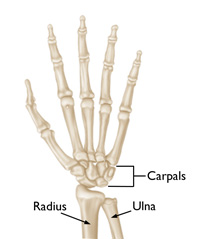

The wrist is a complex joint that connects the hand to the forearm. It is formed by the two bones of the forearm—the radius and the ulna—and eight small carpal bones. The carpal bones are arranged in two rows at the base of the hand. There are four bones in each row.

The joint surface of each bone is covered with articular cartilage—a slippery substance that protects and cushions the bones as you move your hand and wrist.

The bones of the wrist. Cartilage coats the ends of the bones to create a gliding joint.

Reproduced from JF Sarwark, ed: Essentials of Musculoskeletal Care, ed 4. Rosemont, IL, American Academy of Orthopaedic Surgeons, 2010.